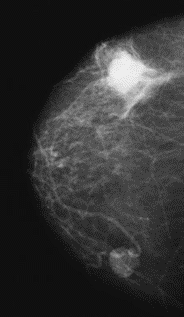

Na którym obrazie rentgenowskim sutka uwidoczniono zmianę patologiczną w obrębie węzłów chłonnych?

A. Obraz 2

B. Obraz 3

C. Obraz 4

D. Obraz 1